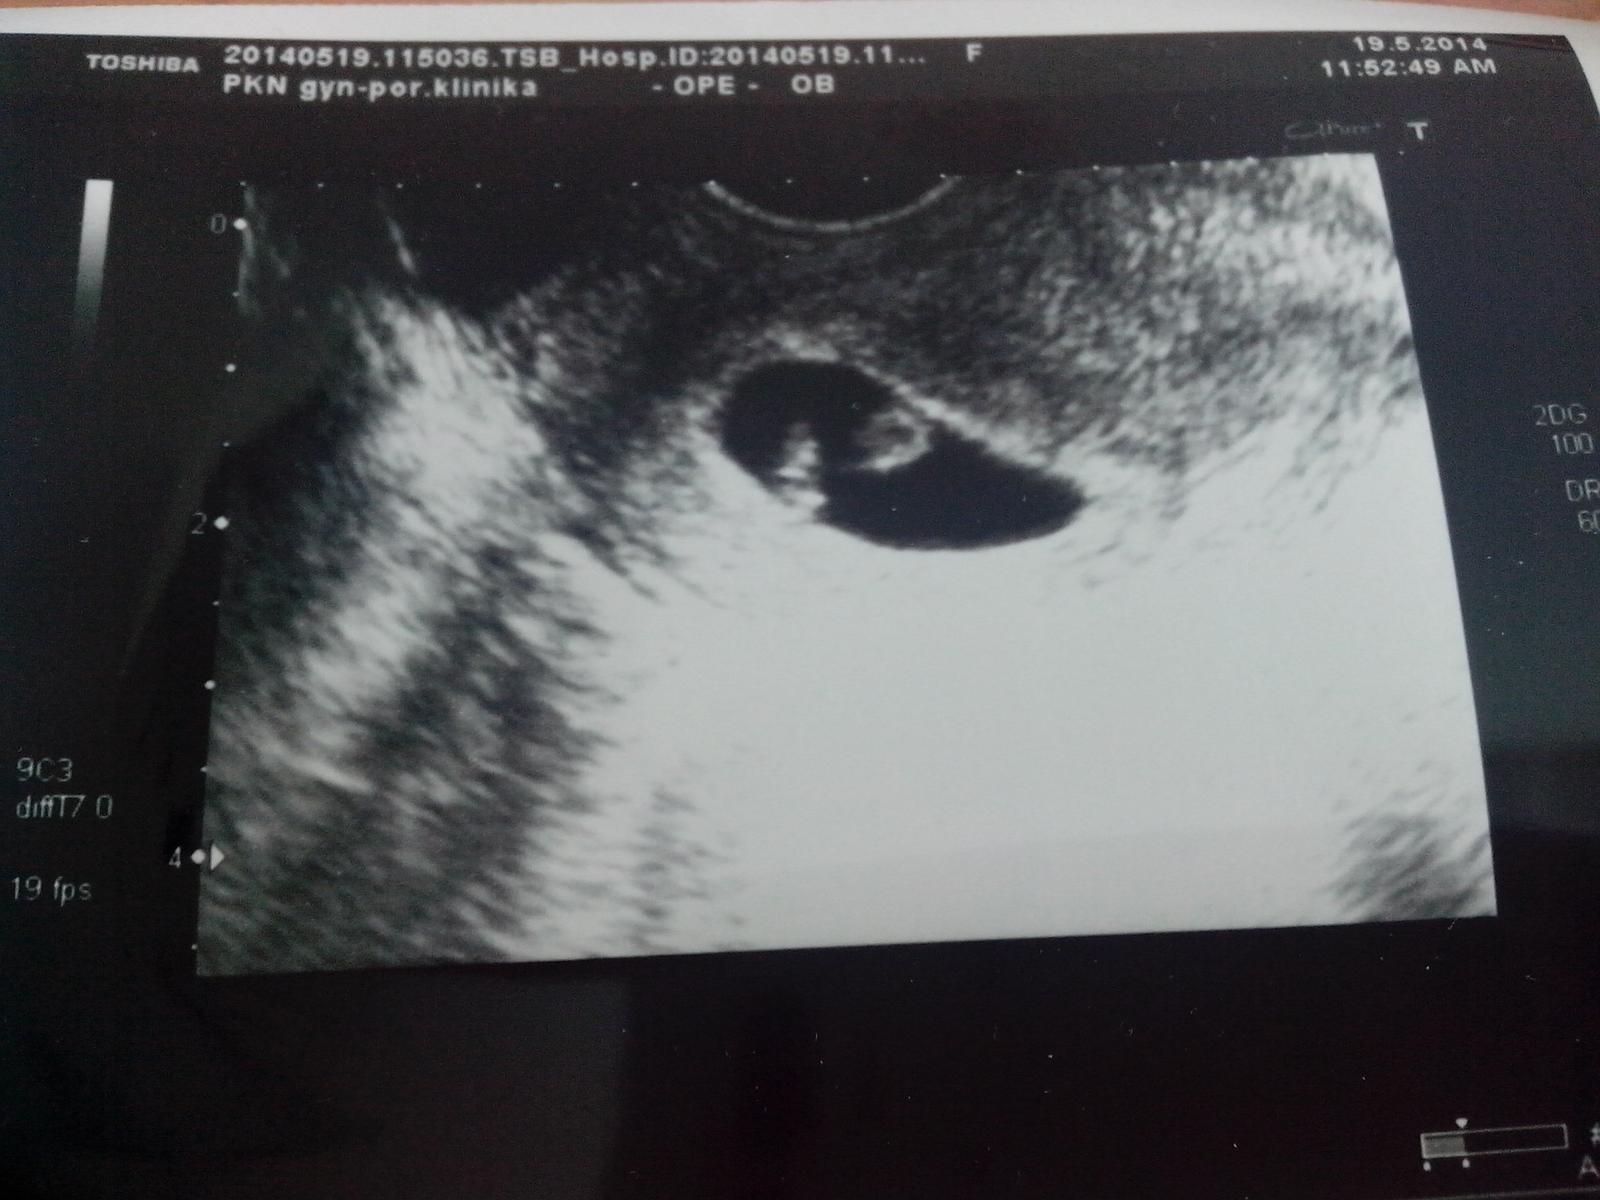

@joannah13 - no krása stíhá nádheru 😵 , to je ale maličká fazolka, tak jen tak dál, ať vám roste do krása, a hodně zdraví pro maminku a miminko a ať si brzy doma v klidu ve svém...

@joannah13 no po pravde, ja tiez neviem, na co sa treba pozerat 😀 ci to cierne velke, alebo tie svetle bodky vnutri... ale ked to tam je, tak to tam je 😅 aj tak je to najkrajsie, ked sa narodi 🙂

@joannah13 no krasne babuliatko malinke. Vidis, hned sa Ti spokojnejsie dycha 🙂 Super sa tesim z Teba, z Vas vlastne 🙂

@paskolinka to cerne je dutinka a ta svetla smouha vlevo je miminko..

@joannah13 aha, uz vidim.. tusim sa aj usmieva 😨 😅

@paskolinka nebo ukazuje pozadi 😀

@senta_sofia bude bude a snad brzy, hezky na obrazek kukaj, at se tim nakazis 🙂

@joannah13 neviem sa vynadivat 🙂) a pustia ta dnes domov? dufam, ze sa nakazim, aj ked vcera som zbalila kocik po malom a schovala...

@joannah13 jeeeej gratulujem ku srdiecku, uz mozete pekne rast do krasy, tesim sa 🙂